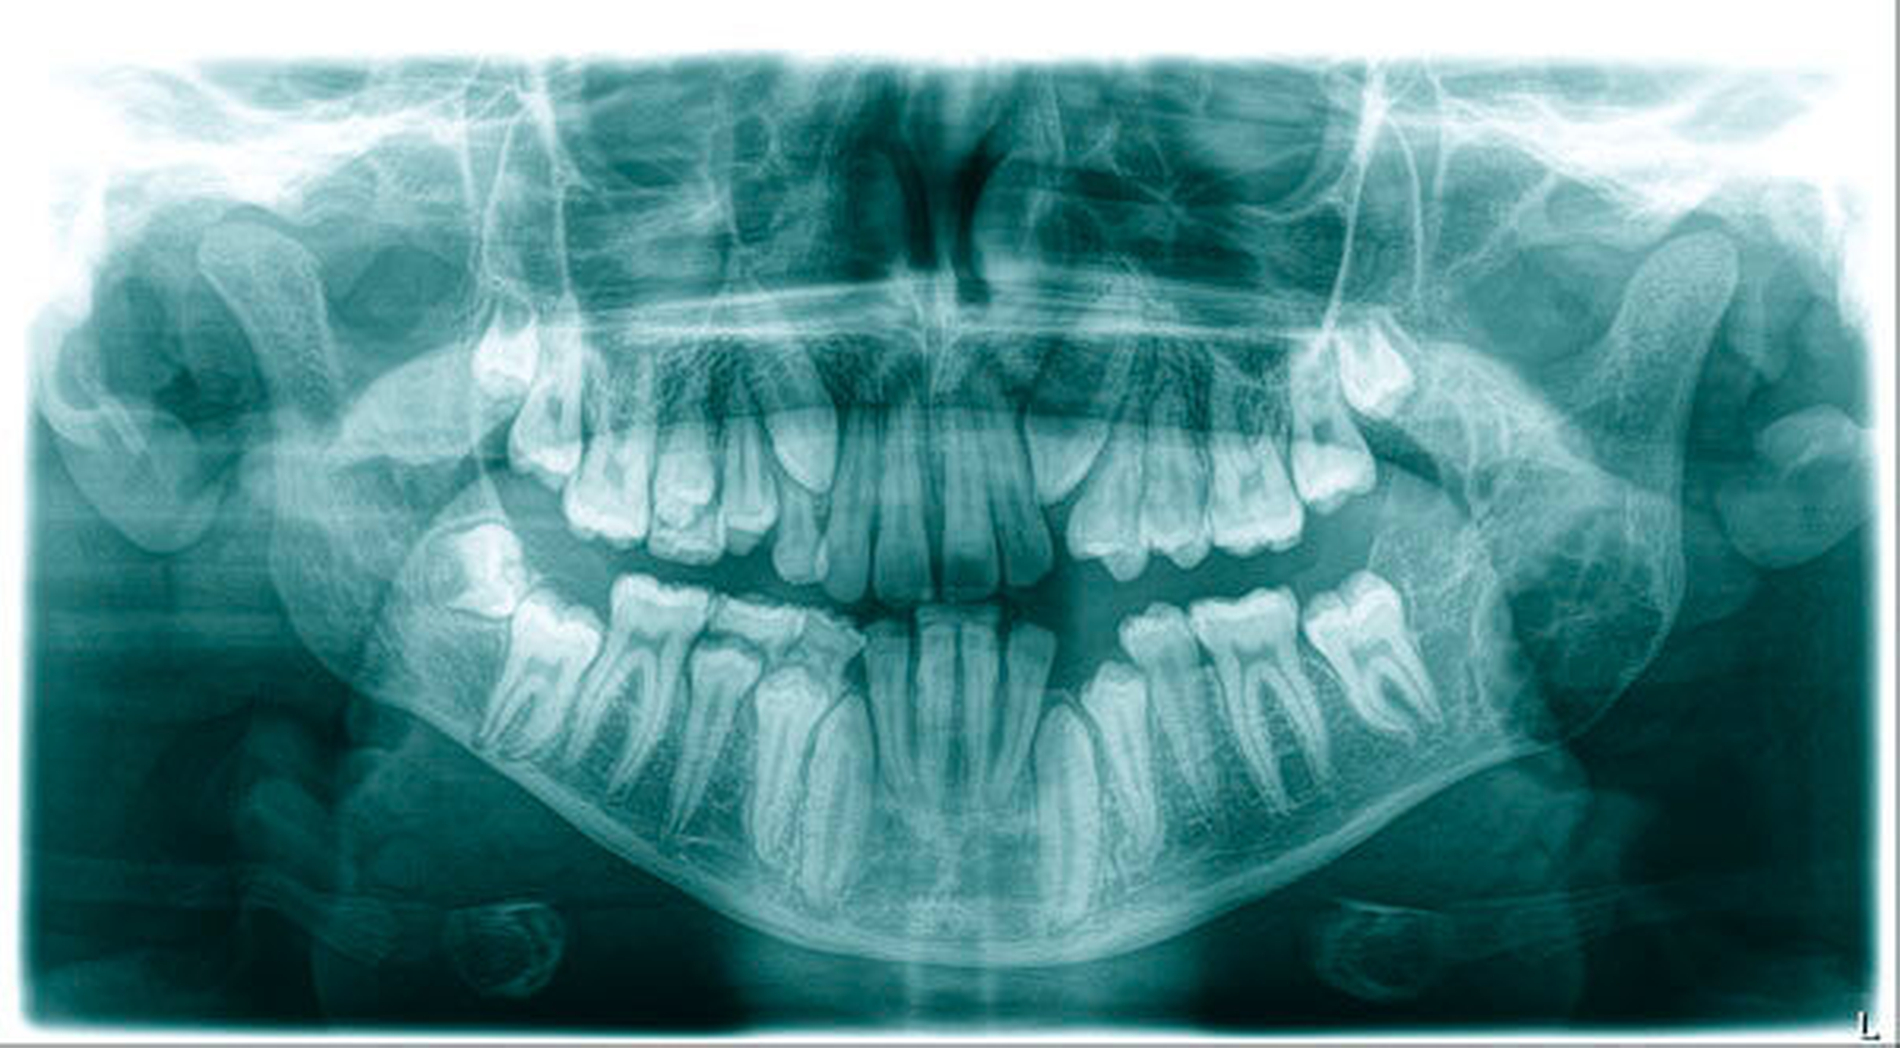

Sechs Jahre vergingen, bis erneut ein kieferorthopädischer Kollege im Zuge seiner Planung bei multiplen persistierenden Milchzähnen auf die radiologisch auffällige Raumforderung im linken Unterkieferast stieß (OPG). Erneut wies der nun 16-Jährige keinerlei Symptome oder Beschwerden auf.

Die Computertomografie zeigte im linken Unterkieferwinkel eine im Ausmaß von 4,2 cm x 1,3 cm große, septierte Raumforderung mit Destruktion der bukkalen und der lingualen Kortikalis.